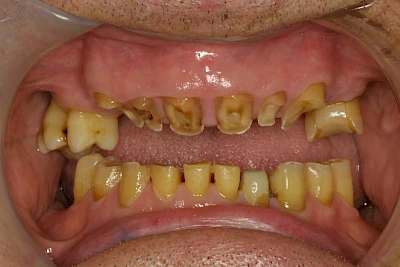

Über die Zeit können verschiedene Prozesse die Zahnhartsubstanzen aufzehren:

- Abnutzung durch Kauen (Abrasion) oder duch durch übermäßiges Knirschen bzw. Pressen (Attrition)

- Säurebedingte Auswaschung (Erosion)

- Knirschen bzw. Pressen und ungünstige Putztechnik (Druck): keilförmige Defekte

Auswaschung

Auswaschung (Erosion) dagegen ist eine Verschleißerscheinung der Zähne aufgrund von immer wiederkehrenden Säureangriffen durch die Nahrung, verstärkt zum Beispiel durch den Genuss säurehaltiger Getränke oder Speisen. Auch bei Menschen mit einer Essstörung (z. B. Bulimie) können die Zähne durch die Magensäure ausgewaschen erscheinen.